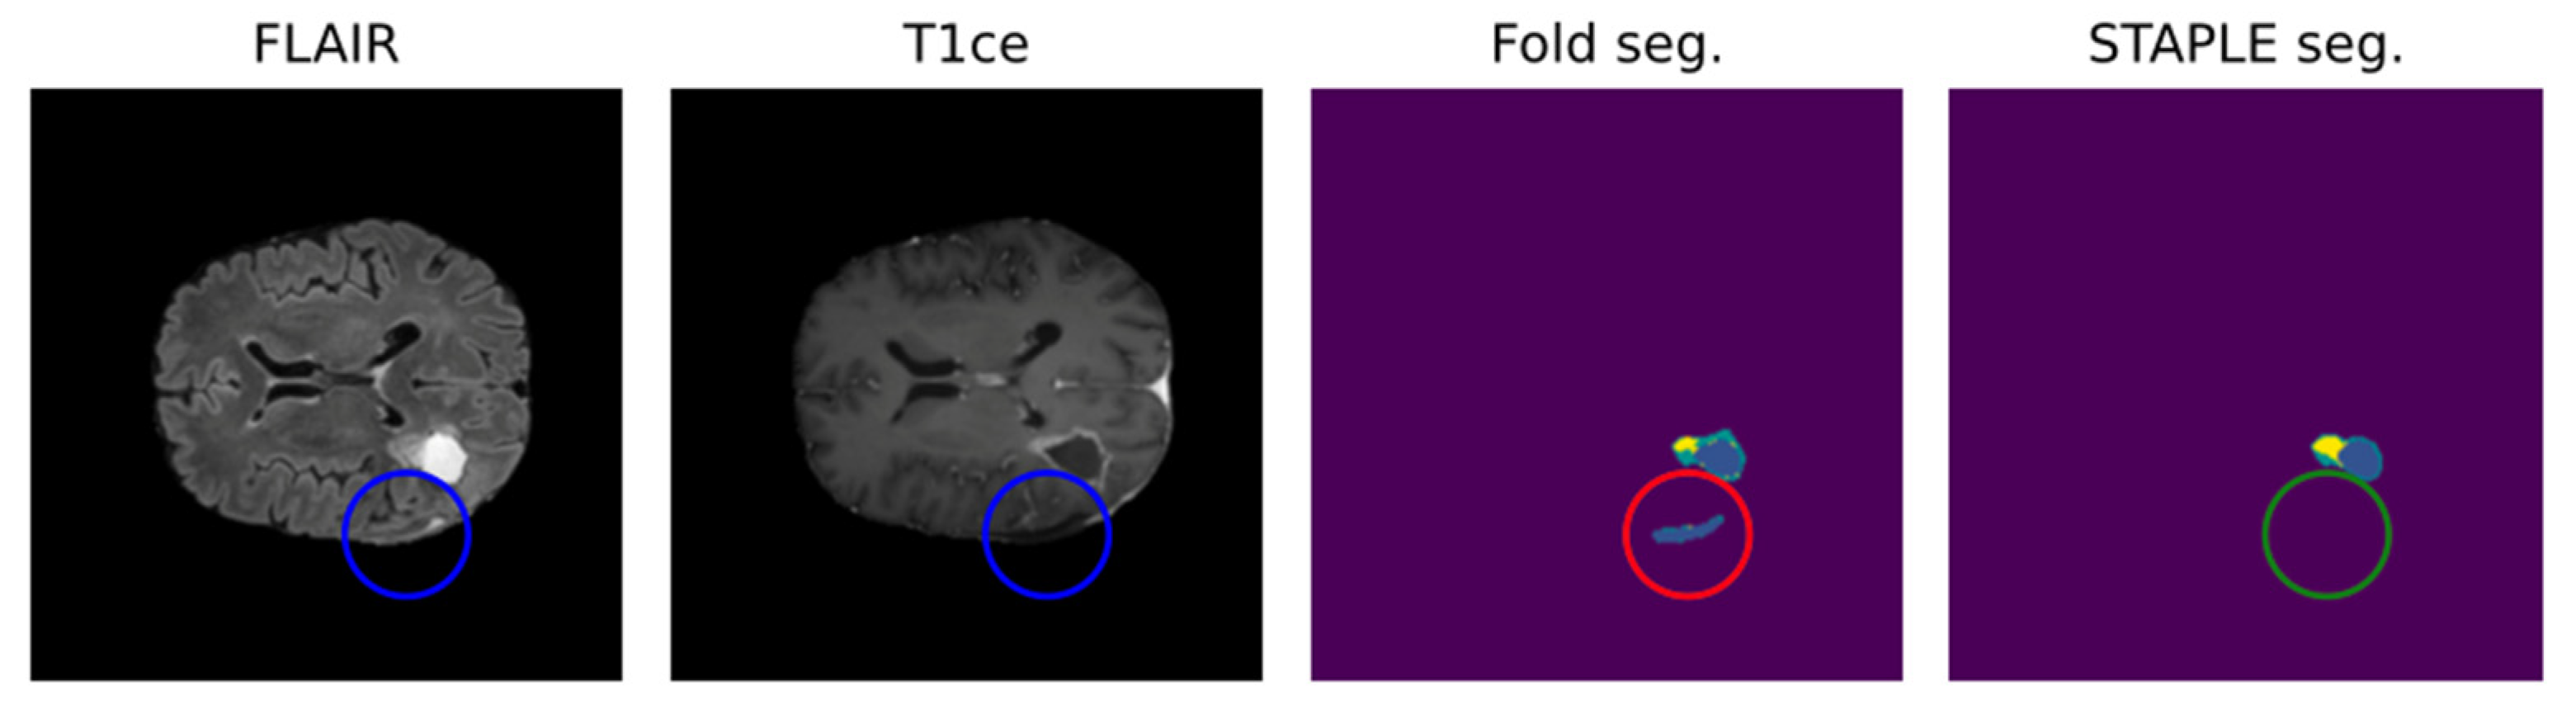

Due to the intrinsic nature of the medical segmentation task, it is hard to consider different ground-truth strategies other than the manually performed labeling. For such reason, common measuring approaches leverage human error subjectivity mitigation trough the averaging of multiple manual segmentations. Annotation averaging is usually performed through tools such as STAPLE, which is based on expectation–maximization and probabilistically corrects noise elements such as outliers or false positives. Usually, this approach is similarly performed for the AI model, exploiting what is known as cross-validation.

Leveraging multiple trained models to aggregate inferences through STAPLE enhances the robustness of AI predictions. Figure 2 shows that STAPLE was able to correct a misclassification case of the resection cavity. Metrics like the Dice Score and Hausdorff distance percentiles are then used to assess the AI model’s true capabilities comprehensively.

Figure 2.

Positive effect of STAPLE fusion for resection cavity segmentation [47]. Results obtained from the fivefold cross-validation process (fold seg.) are merged by the STAPLE algorithm to obtain a final result (STAPLE seg.). The figure shows, as an example, how the STAPLE convergence is able to recognize oversegmentation of a hypointense region misclassified as resection cavity (blue: cavity; yellow: enhancing; green: whole).